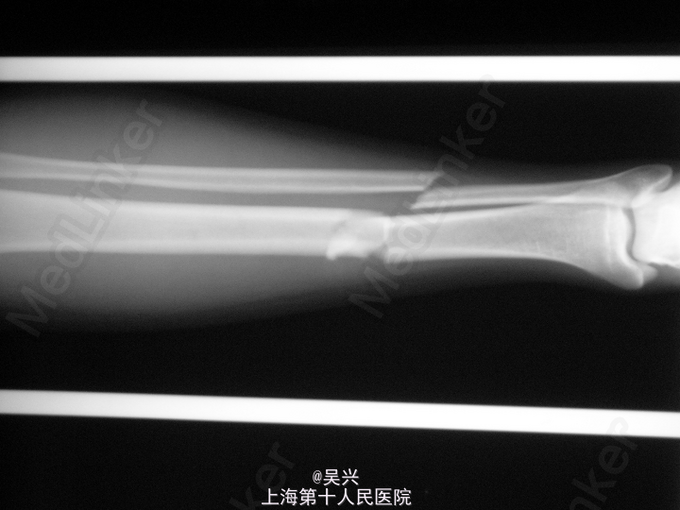

车祸致右小腿肿痛、畸形1小时,急症入院。

查体:右小腿中下段肿胀、畸形、触痛,反常活动。 辅查:X线片市右胫腓骨中下1/3骨折,移位。

诊断:右胫腓骨中下段骨折。 处理:入院后予跟骨牵引,抬高患肢,甘露醇脱水消肿,4天后行腓骨远端骨折切开复位钢板内固定,胫骨骨折闭合复位、髓内钉内固定。